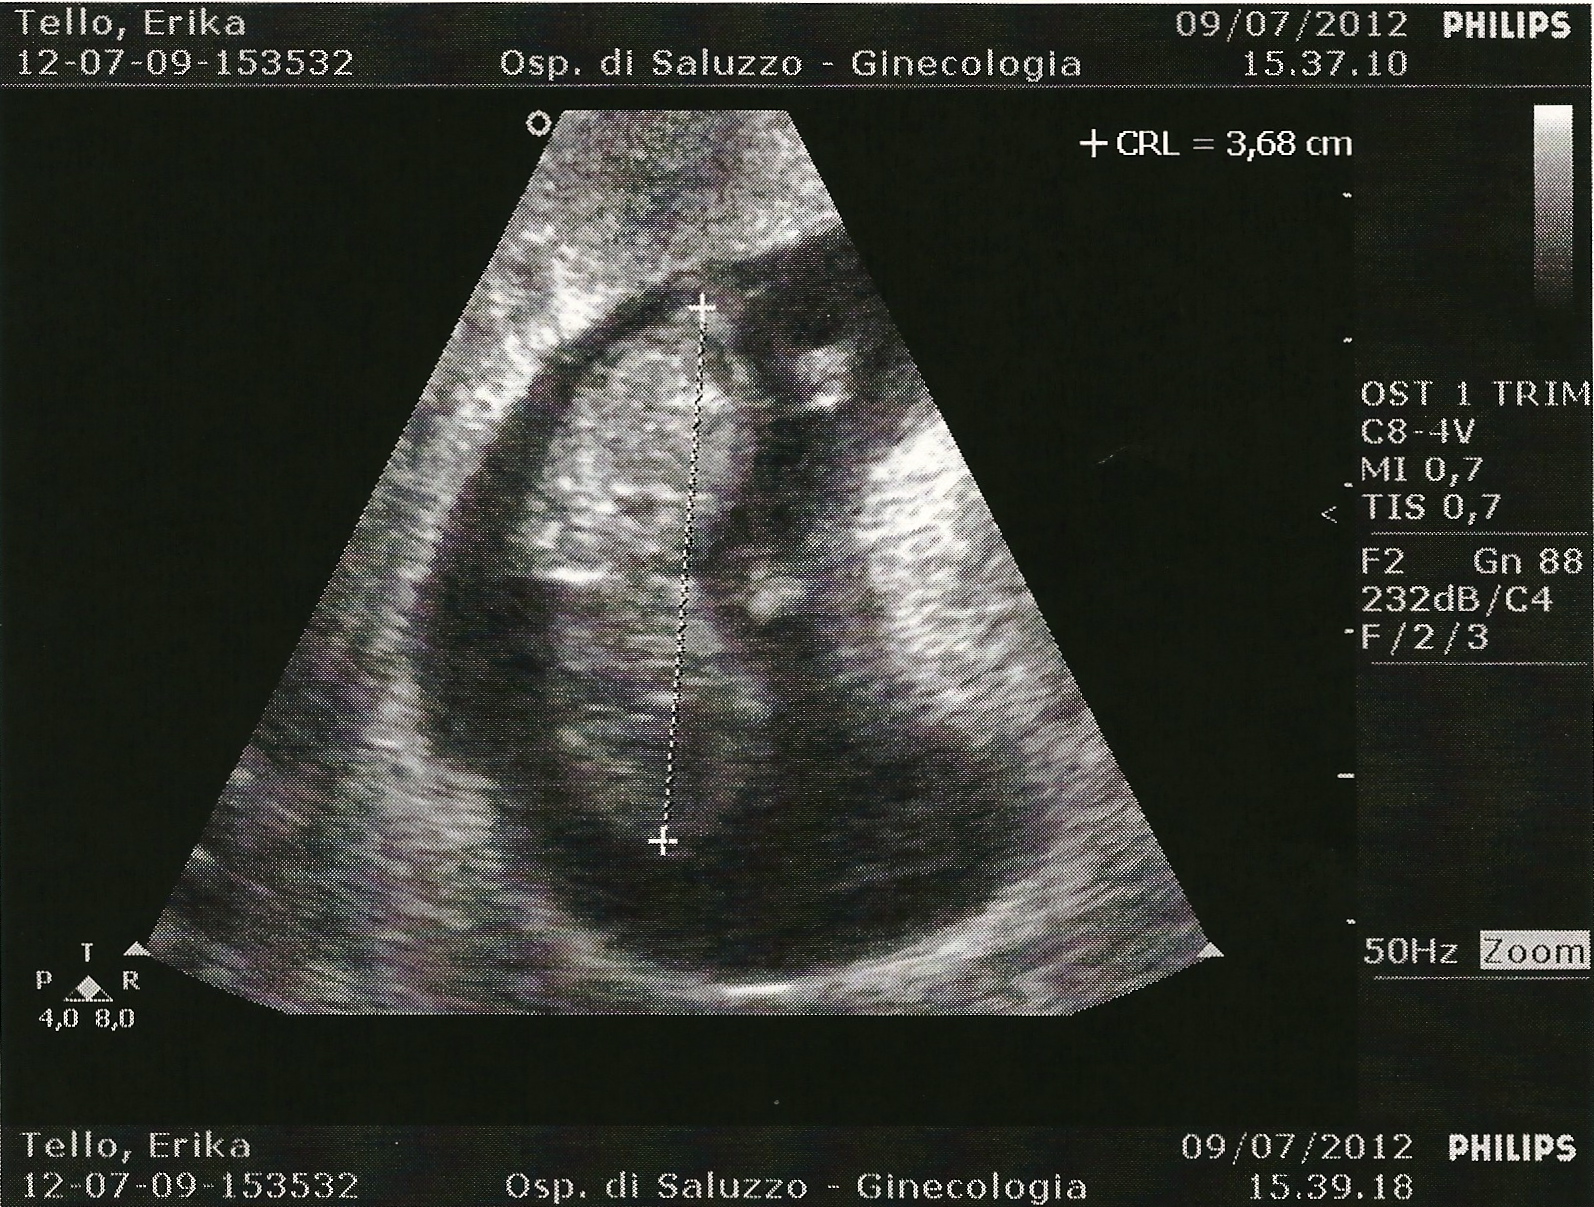

And now I proudly present to you, the first pictures of our baby!

We are praising God tonight for a healthy baby and pregnancy thus far and looking with new expectation toward his or her expected arrival on (or around) January 31st!